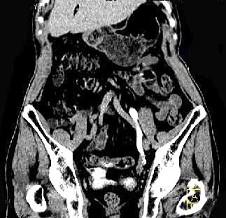

问题 男,76岁,无痛性肉眼血尿3个月,CT检查如图所示,下列说法错误的是 ( )

选项 A、考虑为左侧输尿管炎 B、考虑为左侧输尿管下段癌 C、左侧输尿管中上段扩张 D、左侧输尿管下段可见节段状不规则的软组织肿块影 E、左侧肾盂扩张积水

答案 A